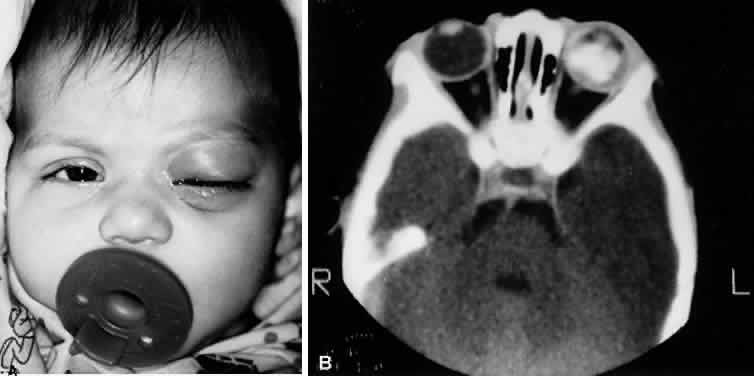

H. influenzae type B cellulitis typically begins with mild upper respiratory tract infection, fever, leukocytosis, and unilateral hyperemia and edema of the soft tissues of the eyelids. A sharply demarcated, purple discoloration of the skin of the eyelids and adnexal region is characteristic (Fig. 12). Mild conjunctival hyperemia and chemosis may be present.

Fig. 12. A. Two-year-old African-American girl with preseptal cellulitis due to type b H. influenzae. B. Seven-year-old white boy with preseptal cellulitis due to S. pneumoniae.